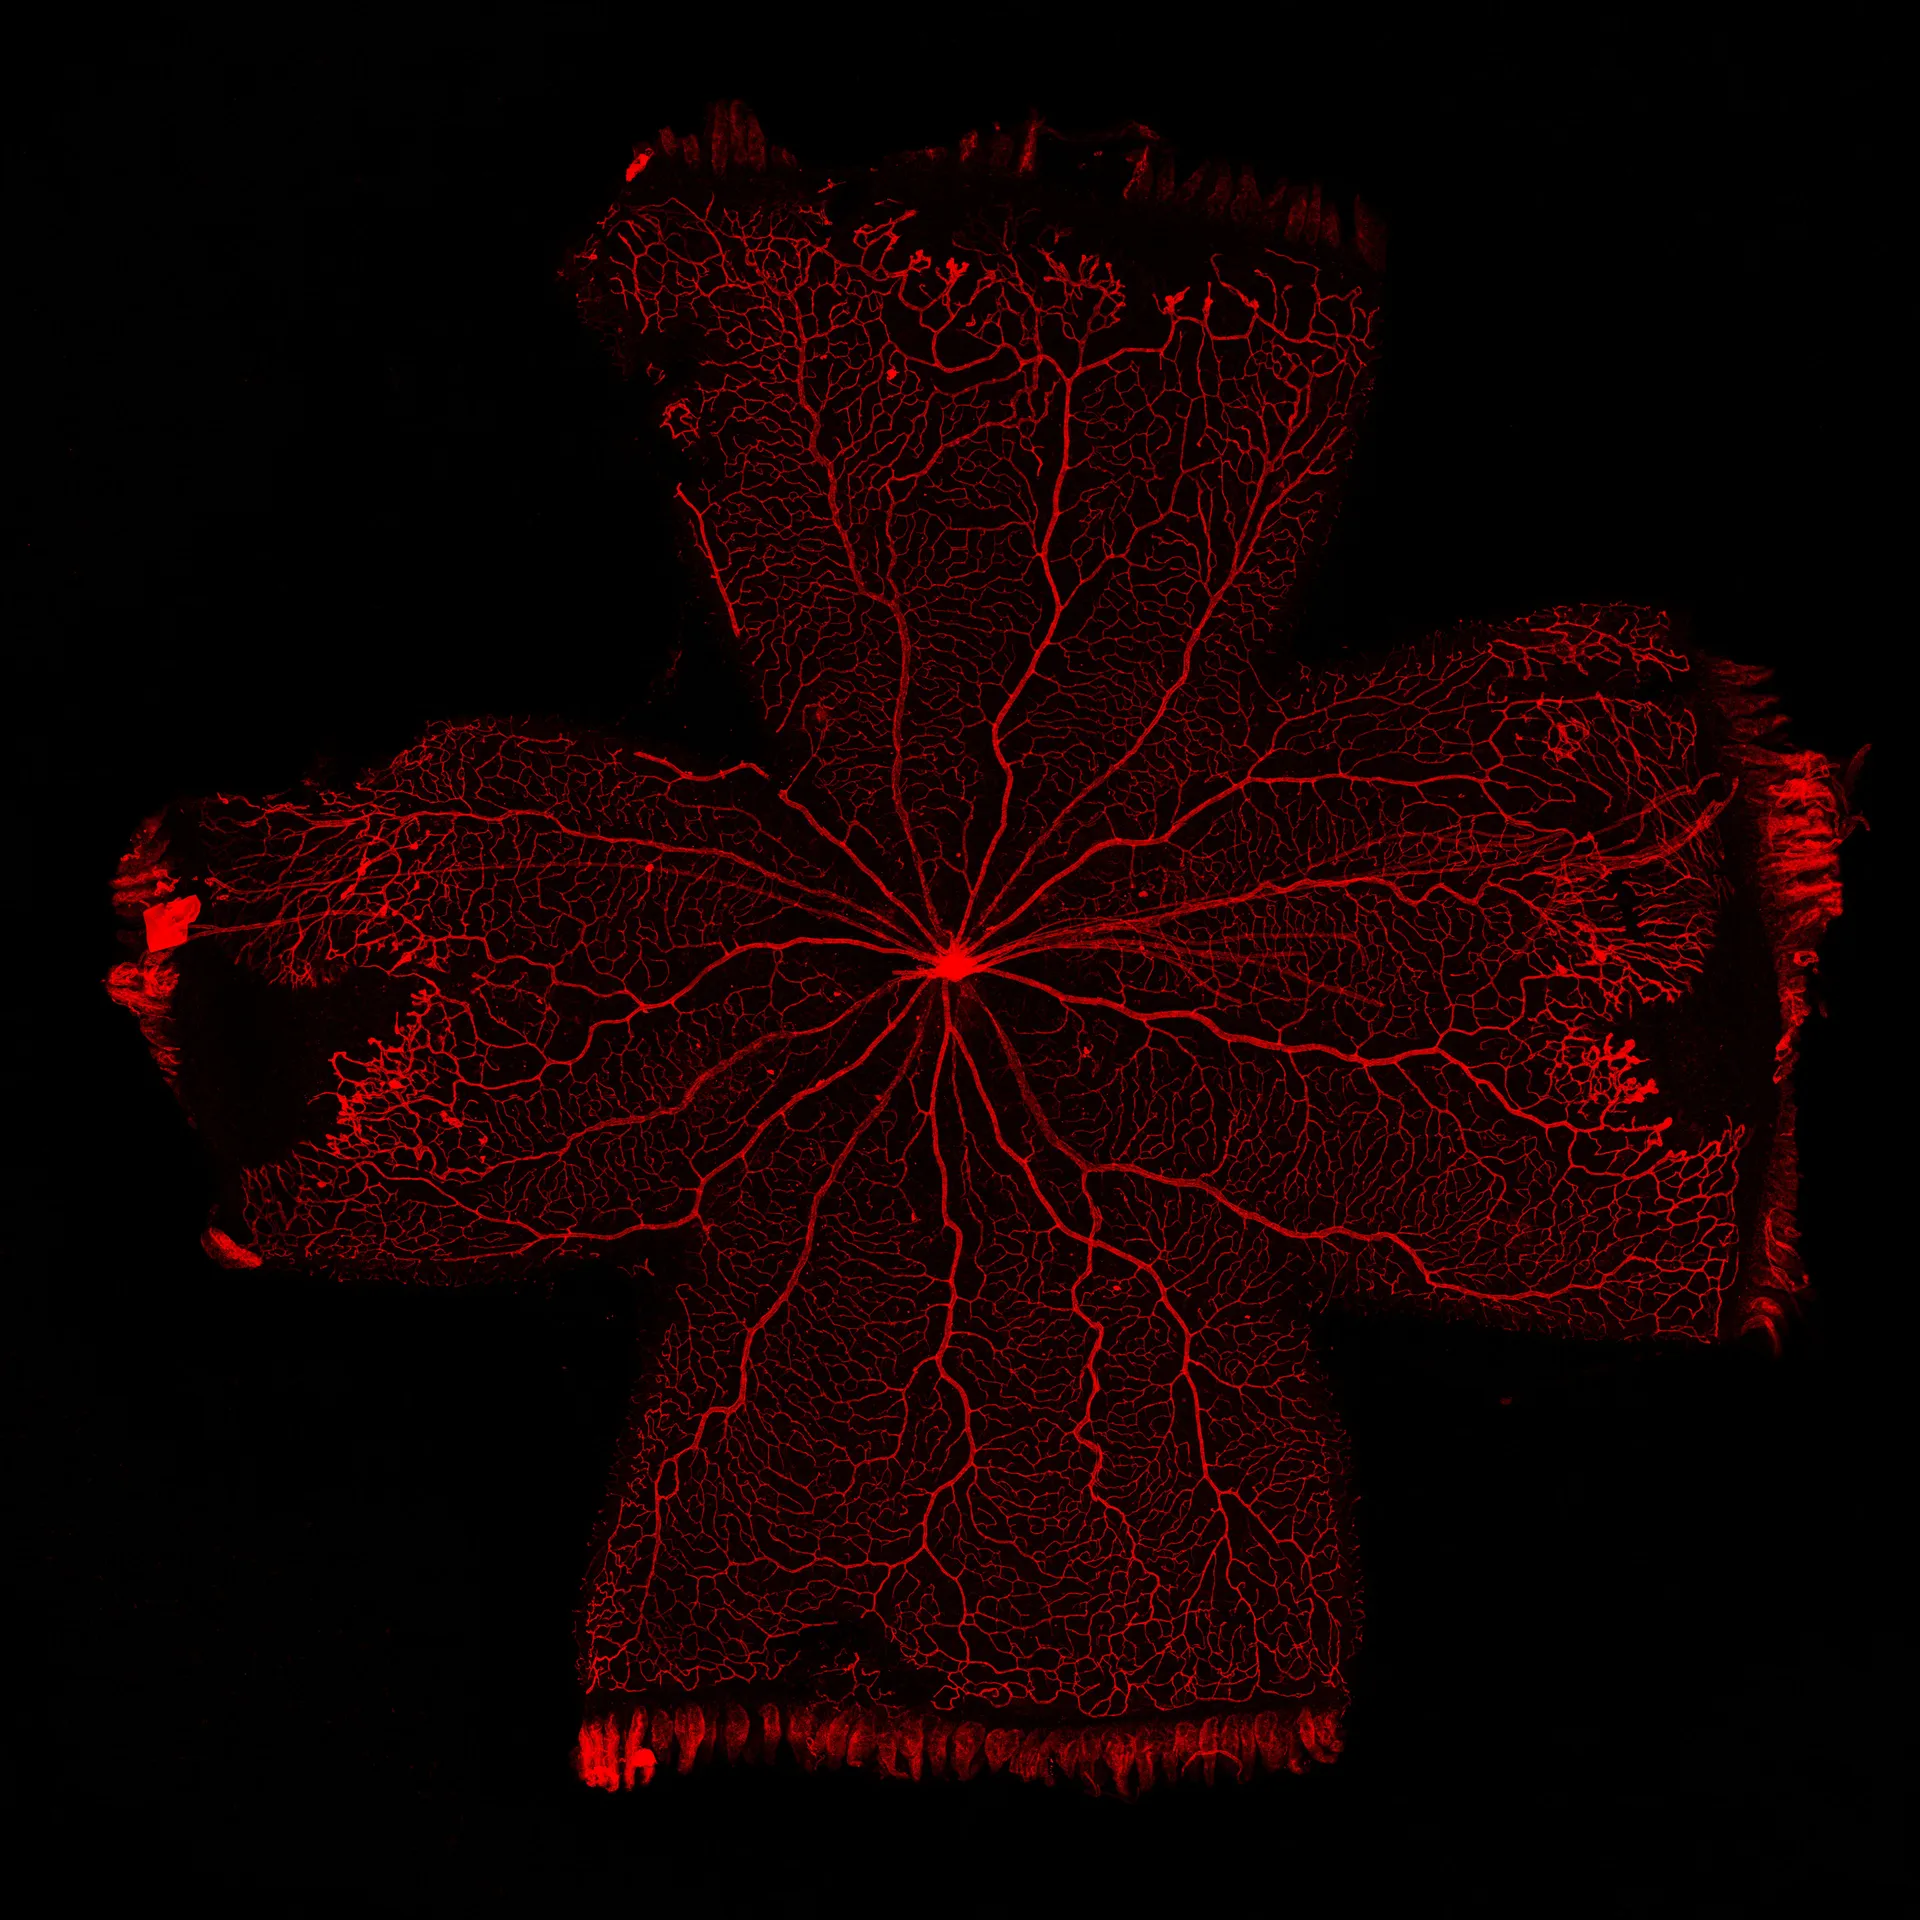

At Experimentica, we have implemented and validated both mouse and rat OIR models with a clinically relevant reference compound making them ideal for screening anti-angiogenic drug candidates. Our capabilities include morphological analysis of retinal vasculature from flat mounts, combined with in vivo imaging, such as fluorescein angiography (FA) and flash electroretinography (ERG).

Analysis of retinal vasculature from isolectin B4 stained flat mounts:

– Avascular area/vascular obliteration

– Area of neovascularization